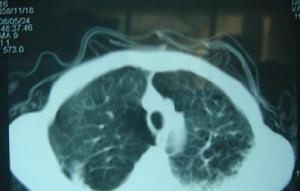

潛伏期3-10 天,多為7天。患兒以腹瀉為主要表現,每日數次至十次,稀水樣便,持續1-2 周,平均8-9 天,少數可持續3-4 周。70%患兒伴有嘔吐,40%患兒以發熱起病,伴有腹瀉。體溫38℃以上,2-3 天后熱退。部分患兒可同時有鼻炎、咽炎、氣管炎等上呼吸道感染症狀。3%-6%有肺炎表現。

3%~6%患者X線有肺炎表現。